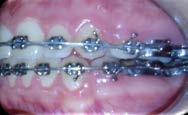

El examen clínico intraoral reveló una clase I molar bilateral, caninos superiores en infraoclusión, por ende la clase canina no se puede clasificar, presencia de apiñamiento severo, rotaciones en premolares superiores e inferiores, línea media inferior desviada hacia el lado derecho 3.5 mm,

Figura 1. Paciente femenina 15 años de edad.

falta de coordinación de las arcadas, el arco inferior con forma cuadrada y el superior forma ovoide, el overjet de 2 mm y el overbite de 2 mm (Figura 2).

Figura 2. Fotografías intraorales iniciales.